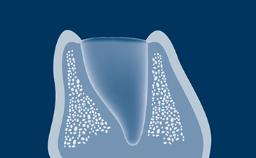

When a tooth is extracted, the alveolar bone that supports the tooth resorbs over time. This resorption results in a reduction in alveolar bone volume, as shown in this clinical example of a missing upper right central incisor. The bone has diminished significantly in orofacial width, and this is in conflict with the fundamental requirement in implant dentistry that implants are placed in the correct prosthodontically determined position. When the alveolar bone resorbs, it is often necessary to augment the bone to ensure that implants can be placed correctly and be completely embedded in bone. This module will describe a specific technique for bone augmentation known as guided bone regeneration or GBR.